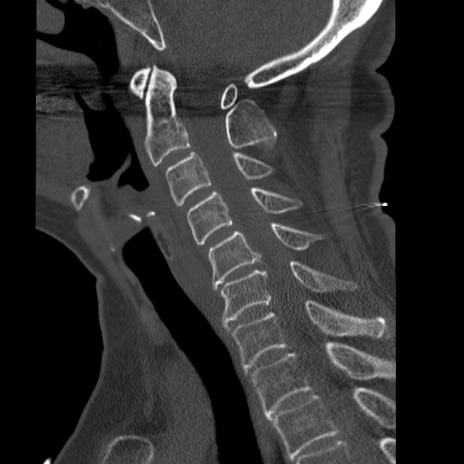

症例50 頚椎CT(矢状断像)

【症例】60歳代女性

【主訴】後頭部〜右後頸部にかけての痛み

【現病歴】本日飲食店でコーヒーを飲んでいたところ、突然後頭部〜右後頸部にかけて痛みが出現し、右上肢の感覚障害を伴ったため救急要請。

【身体所見】脳神経学的に明らかな異常所見を認めず。右上肢に軽度の感覚障害あり。

異常所見と診断は?

頚椎CT

冠状断像